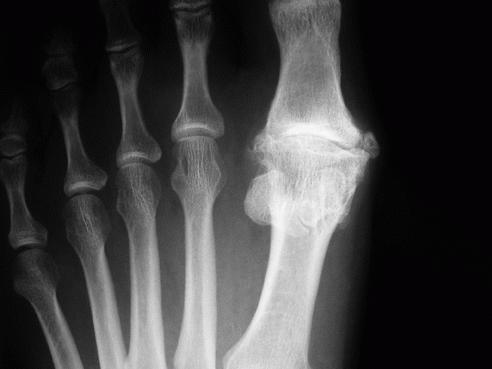

- Ревматоидный артрит. Возникает в любом возрасте и поражает практически все суставы пальцев ног, что может привести к их полнейшей деформации. Также страдает соединительная ткань и весь организм в целом. Артрит пальца ноги данного вида может стать причиной инвалидности человека.